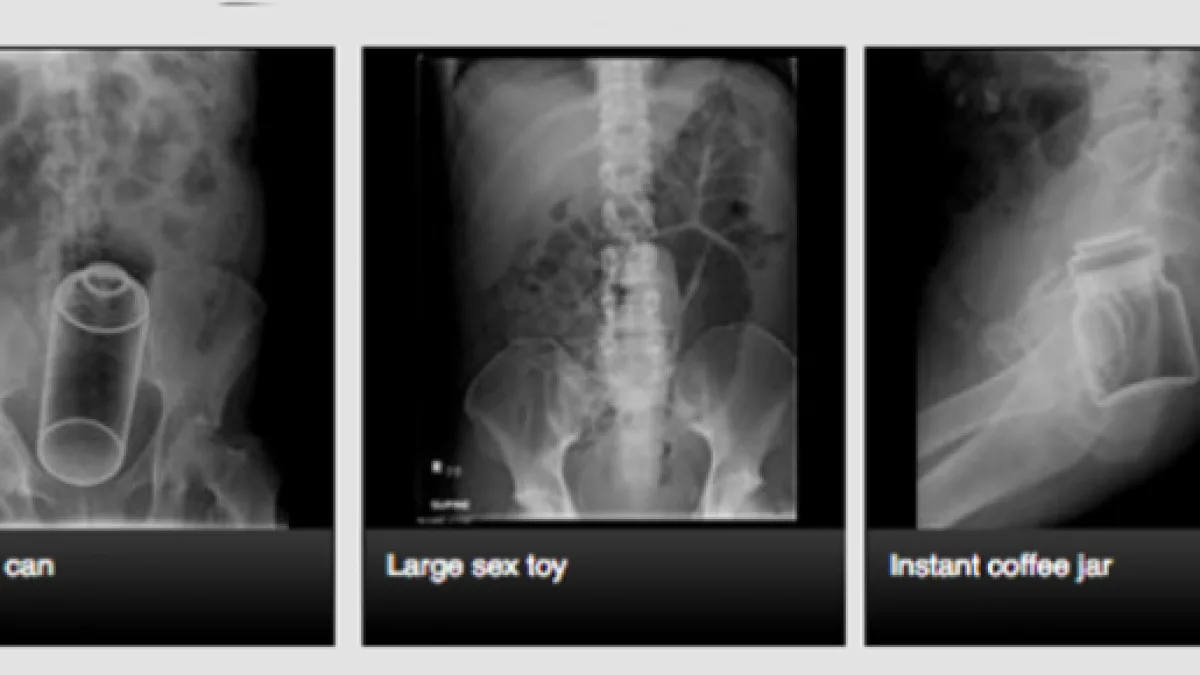

Anche se i sanitari del pronto soccorso devono essere pronti a intervenire in ogni genere di circostanza, contesti simili, oltreché essere di difficile risoluzione, creano forte imbarazzo. Questo genere d' emergenze sono impegnative perché, come ci spiega un sanitario, il retto agisce come un aspiratore e l'introduzione risulta molto più semplice dell'estrazione. Il medico, mostrando le radiografie, ci rivela di essersi trovato di fronte a risolvere casi paradossali e racconta gli episodi che gli sono rimasti impressi nella memoria per la loro peculiarità.

Tra questi, il caso di una donna i cui dolori al ventre erano causati da una bottiglia di un litro e mezzo, svuotata della bevanda originale e riempita d'acqua tiepida prima di essere inserita. Per risolvere situazioni simili è d'obbligo intervenire con un'operazione chirurgica. Gli oggetti inseriti, riferisce il medico, sono i più svariati.

Un uomo si è rivolto al pronto soccorso a causa di due mele posizionate nel retto, un altro aveva inserito nell'orifizio una torcia e in altri casi i malcapitati avevano introdotto delle bombolette spray. I medici devono spesso estrarre statuette di svariate forme e dimensioni dal retto.

Un caso di particolare bizzarria è quello di una signora che si è presentata in ospedale in quanto aveva introdotto un barattolo di marmellata. Gli sventurati, per giustificare queste strane intrusioni, affermano il più delle volte di essere caduti sull'oggetto senza averlo fatto intenzionalmente.